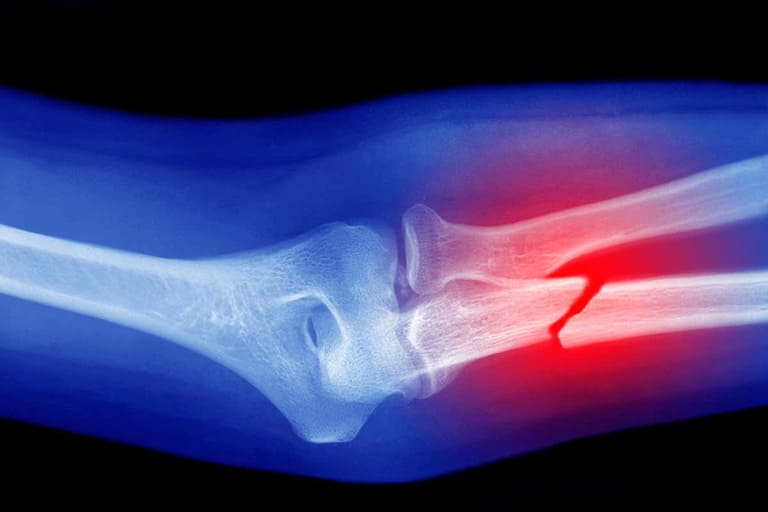

• Gãy xương thường là kết quả của chấn thương như tai nạn xe hoặc ngã. Có nhiều loại gãy xương khác nhau được phân loại dựa trên tính chất và vị trí của vết gãy.

Gãy xương là vấn đề khá thường gặp và có thể xảy ra ở mọi độ tuổi